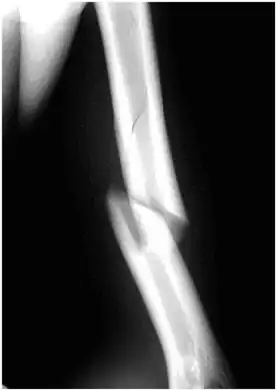

| An x-ray image of a spiral fracture to the left humerus of a 27-year-old male. The injury was sustained during a fall. | |

Internal rotation view showing a spiral fracture at junction of middle and distal thirds of humerus.